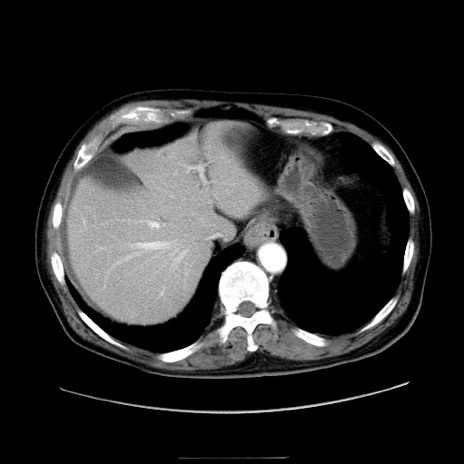

症例30(横断像)

【症例】80歳代男性

【主訴】臍周囲痛

【現病歴】約6時間前から臍下部痛が出現。次第に腹部膨隆・背部痛も生じてきたため来院。背部痛の場所は変化しない。

【既往歴】腎盂腎炎

【身体所見】意識清明、BT 36.3℃、BP  131/87mmHg、P 87bpm、SpO2 100%(RA)、臍周囲自発痛・圧痛あり、反跳痛なし、自発痛部位に一致して板状硬あり、腹部膨隆、腸雑音減弱、CVA tenderness両側陰性。

【データ】WBC 19600、CRP 0.33